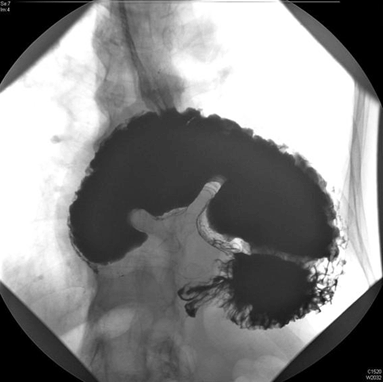

A 73-year-old male presented to the emergency department with a one-day history of severe epigastric pain with vomiting progressing to dry retching. He admitted to a long history of esophageal reflux symptoms treated with oral omeprazole. His initial examination revealed a tachycardia and a swollen, tender epigastrium but no other signs of note. A nasogastric tube was passed with difficulty, he was made nil by mouth and treated with intravenous crystalloids. Laboratory blood results were unremarkable including normal amylase and liver function tests. A chest X-ray showed a large retrocardiac viscus reported as a large hiatus hernia while his abdominal film demonstrated a paucity of bowel gas (Figure 1). An abdominal and thoracic computed tomography (CT) scan revealed a moderate hiatus hernia without obvious perforation and the possible appearance of a rotational component of the stomach with dilatation to the pylorus and no fluid beyond this point. A subsequent upper gastrointestinal contrast study clearly demonstrated an 'upside-down stomach' sign and established the diagnosis of an obstructing organoaxial volvulus secondary to a paraesophageal hiatus hernia (Figure 2) [1]. On transfer to our facility the patient went on to have definitive laparoscopic gastropexy surgery involving reduction of the volvulus, excision of the hernia sac, re-approximation of the diaphragmatic crura then placement of four sutures anchoring the greater curvature of the stomach to the abdominal wall. He has had no recurrence of the volvulus and was symptom free when followed-up in clinic for six months. | ||||||

Gastric volvulus is an abnormal rotation of the stomach through more than 180 degrees, first described by Berti in 1866 [2]. This can lead to ulceration, perforation, hemorrhage, ischemia or necrosis [1]. The non-operative mortality rate is as high as 80% [3]. Adults with acute gastric volvulus typically present with epigastric pain and distension, unproductive vomiting and difficulty with nasogastric tube insertion. A constellation known as Borchardt's triad [4]. About 10–20% of cases occur in children, in adults it can occur at any age but is more common after the fourth decade of life [1] [5] . Gastric volvulus can be classified according to the axis around which the stomach rotates. In organoaxial volvulus, the stomach rotates around an axis connecting the gastroesophageal junction with the pylorus. This is the most common type of gastric volvulus occurring in approximately 60% of cases and commonly leads to strangulation and necrosis [6]. In mesenteroaxial volvulus, there is a transverse axis and the antrum rotates antero-superiorly so that the posterior surface of the stomach lies anteriorly. It is also possible to have a combined type volvulus. The most common causes of gastric volvulus in adults are diaphragmatic defects. In the case of paraesophageal hernia related volvulus, as we report, the gastroesophageal junction remains in the abdomen, whereas the stomach ascends adjacent to the esophagus, resulting in a horizontally lying, upside down stomach [2]. X-ray appearances include a retrocardiac gas/fluid filled viscus on chest film if the stomach is in the thorax and a paucity of distal gas on plain abdominal film [7]. Several authors recommend computed tomography imaging as the diagnostic method of choice, this may show a torted bi-lobular stomach with a transition line [2] [8] [9]. However, the diagnosis of gastric volvulus is classically based on upper gastrointestinal contrast studies using barium or Gastrografin. These studies are both sensitive and specific if performed in the twisted state and classically show an upside-down stomach' sign as well as illustrating the degree of obstruction [8]. Endoscopic reduction of gastric volvuli is possible but recurrence rates are high if this is performed as an isolated procedure [2]. Surgical repair was traditionally based on an open approach but this has been superseded by modern minimally invasive techniques. Laparoscopic suture gastropexy, as described in our case, is safe and effective for both acute and chronic gastric volvulus [1] [2] [3] . | ||||||

Acute gastric volvulus is a rare surgical emergency with high rates of non-operative mortality. Prompt diagnosis and urgent surgery is crucial to avoid life-threatening complications associated with this condition. A purely clinical diagnosis is challenging but the condition should be suspected in a patient who presents with abdominal pain and distension, unproductive vomiting and a difficult to place nasogastric tube. Although a computed tomography scan may prove useful our case report clearly demonstrates the power of upper gastrointestinal contrast studies in establishing a definitive diagnosis. | ||||||